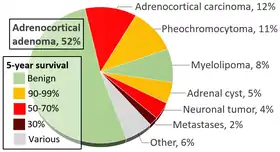

As suggested above, incidental imaging has become a major player in the diagnosis of patients with pheochromocytoma, with current estimates between 10–49% of all cases diagnosed after imaging was obtained for another reason. When an adrenal nodule (potential tumor) is discovered on computed tomography or magnetic resonance imaging, there is between a 5 and 10% chance the lesion is a pheochromocytoma.[171] The incidence of adrenal tumors is found in the infographic above, with pheochromocytoma noted in yellow in the top right corner.